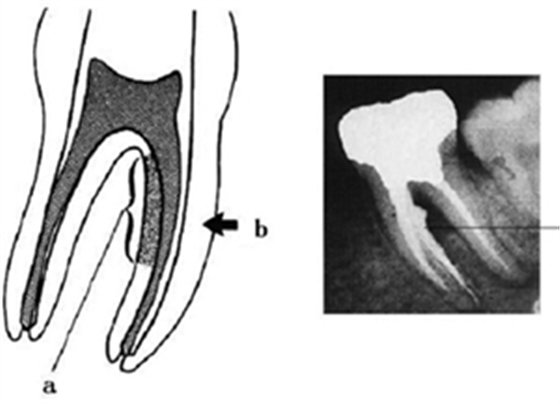

2.根管在x線片上是一種2維的圖像,所以雖然有時片子上表現(xiàn)為直的,但事實上根管是一個三維的空間,顯示沒有近遠中向的彎曲,卻可能向頰舌向彎曲,這種頰舌向彎曲的信息是平常臨床上無法獲得的。所以很少有完全直的根管。幾乎所有的根管都有一定程度的彎曲.尤其在根尖部。最后這句話幾乎可以當(dāng)作一個定理。我們看下面一張關(guān)于根尖孔的圖。

a. 根尖孔開口于正常根尖頂部 (56.53%)

b. 根尖孔開口于牙根尖的唇或舌側(cè)

c. 根尖孔開口于牙根尖的近中或遠中面

正常情況下根尖孔開口于根尖頂部(圖a),這是我們工作中最常見到的影像,但這種情況只有 56.53%,所以還有將近一半的情況是其他的開口形式。圖b就表明根尖孔的開口在唇舌向,當(dāng)我們見到這樣的根尖片的時候,要引起足夠的重視,有一個特殊的這種情況就是下第二磨牙“C”型根管的術(shù)后影像,常會有這樣的表現(xiàn)。這種研究國外并沒有做的很到位,因為他們很少遇到這種牙齒,到是黃種人的下7常見這種影像,國內(nèi)還是武漢研究的比較多。以后的內(nèi)容會有相關(guān)的討論。

圖3表明的內(nèi)容在這種示意圖上比較好懂,但臨床工作中,有醫(yī)生容易以為是自己側(cè)穿了,或者其他的什么情況,當(dāng)然根尖片拍的好壞也很有關(guān)系。